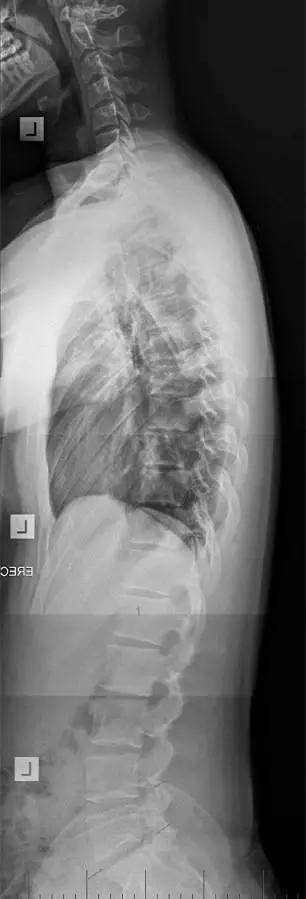

图一:这是一个16岁女孩的X线片,可以清晰的看见弯曲的椎体,这个女孩正在慢慢变成驼背!

图二:是一个17岁男孩的X线光片!